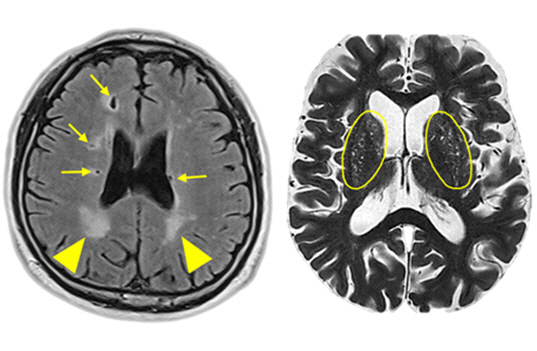

뇌혈관이 막히거나 터지는 질환을 부르는게 뇌졸중이고 그 중 뇌혈관이 막히는게 뇌경색 그리고 뇌혈관이 터지는 것을 뇌출혈이라고 합니다. 뇌졸중은 영구적인 손상이 많다고 하며 증상에 따라 전신이나 육체 일부 기능이 마비되는 등의 극심한 후유증이 남는 무서운 질병입니다 오늘은 뇌경색 초기증상에 대하여 알려드리도록 하겠습니다.

허혈성 뇌졸중은 발생 기전에 따라 대혈관 질환에 의한 뇌경색, 심인성 뇌경색 또는 심인성 뇌경색, 소혈관 질환 또는 틈새 뇌경색, 기타 드문 이유가 되는 것에 의한 뇌경색으로 나누어져요. 에피소드는 일정 기간 동안 증상이 완전히 가라앉는 경우입니다.

허혈성 뇌졸중의 대표적인 이유가 되는 것은 고혈압, 당뇨병, 고지혈증 등으로 인해서 뇌에 혈액을 전달하는 혈관에 동맥경화(동맥경화)가 발생하여 뇌로 가는 혈류를 차단하는 것입니다.